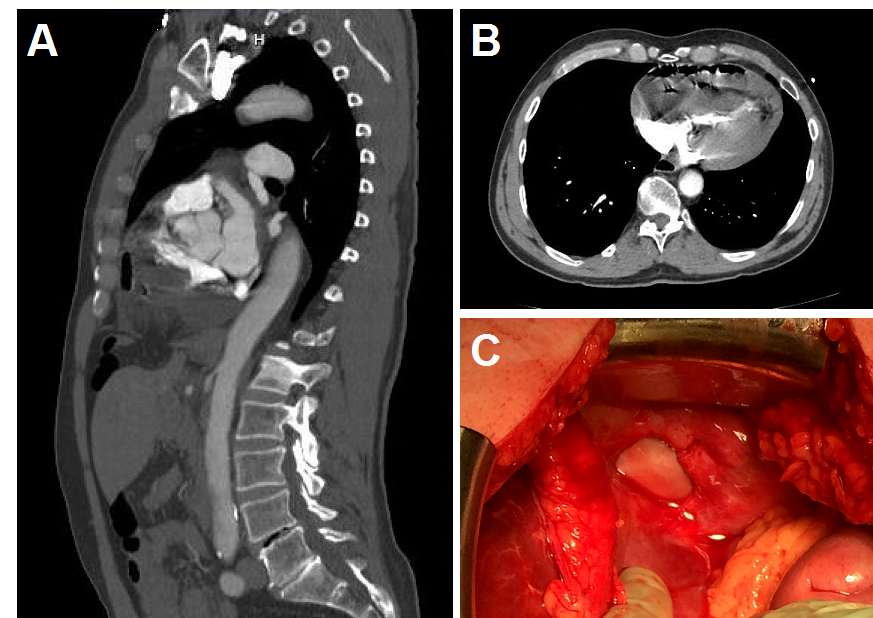

Figure 1. (A) Sagittal CT image showing diaphragmatic defect with small bowl herniated into the pericardium. (B) Axial CT image showing intrapericardial loop of small bowel compressing the chambers of the heart causing cardiac tamponade. (C) Photographic image of the defect in the diaphragm after reduction of intestinal contents.

Two and a half years later, the patient presented with acute onset of severe epigastric pain and associated nausea and vomiting. Concern for possible aortic dissection prompted a computed tomography angiogram of the chest, which revealed the small bowel herniated through the diaphragmatic defect with ventricular compression. Although initially stable, the patient became hemodynamically unstable during transfer and on arrival was on multiple vasopressors. His abdomen was rigid with peritoneal rebound tenderness. Initial laboratory evaluation revealed an arterial pH of 7.04 with a base deficit of 17, an anion gap of 21, and lactate of 8.4. He was taken emergently to the operating room for exploratory laparotomy. Reduction of the herniated small bowel through the diaphragmatic defect from the CP resulted in immediate restoration of normal hemodynamics. A 20 cm in length of infarcted jejunum was resected and primarily reconstructed. The 2 cm defect in the central tendon of the diaphragm could not be approximated primarily due to tension. Because of the potential contamination from the infarcted small bowel, the falciform ligament was secured in a circumferential fashion over the defect with a running 2-0 Prolene® suture. The patient did well postoperatively and was discharged home six days later.